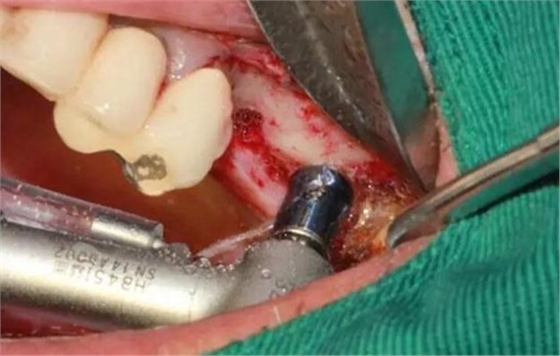

右上5頰側(cè)粘膜竇道,腫脹,膿性分泌物

右上5拔牙窩內(nèi)掻刮出大量肉芽組織

剝離右上6,7頰側(cè)

MASAL工具內(nèi)提升永磁鉆--這就是本病例改良開窗的關(guān)鍵

安全地在上頜竇外壁鉆一個洞